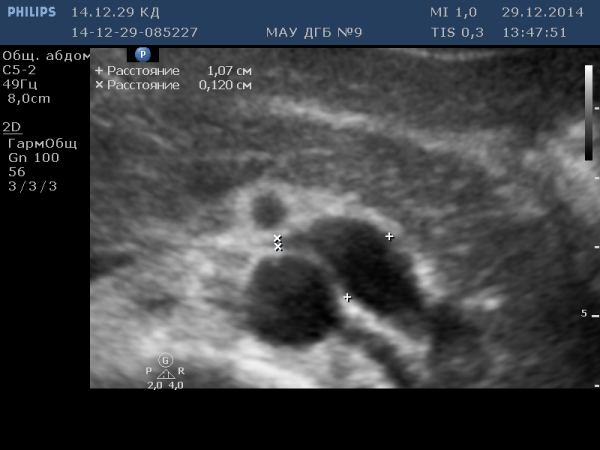

Вот пример из практики. У пациента (подростка) варикоцеле слева 3 степени. Фото - на уровне аортомезентериального отдела. Определяется расширенная левая почечная вена.